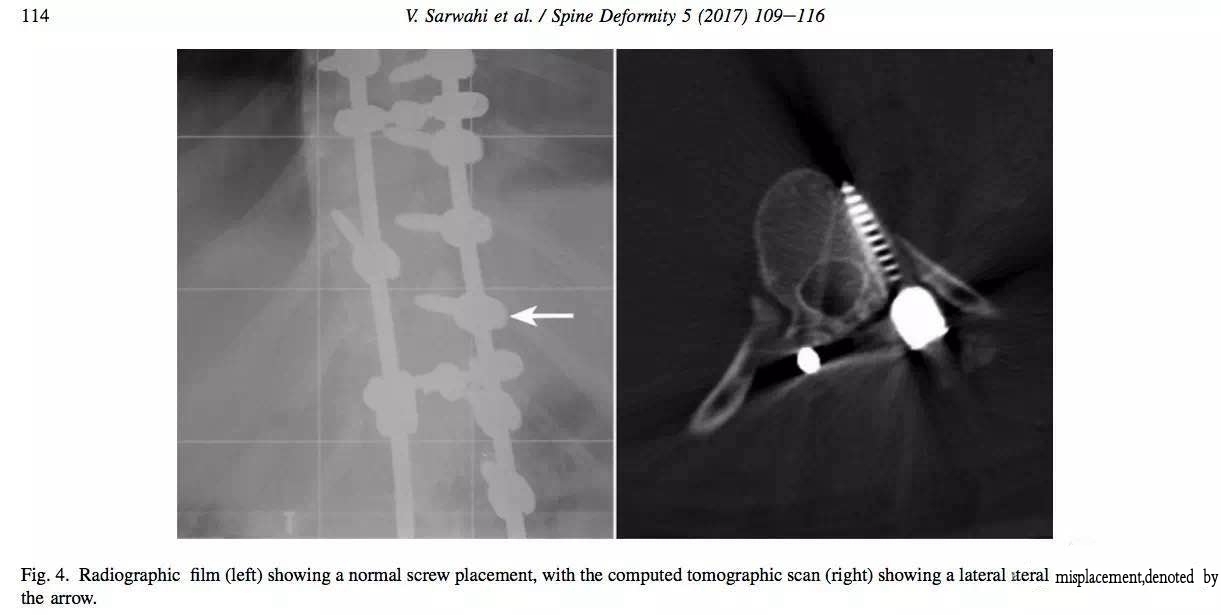

X线片显示钉道足够内倾,但CT复查显示钉子出去了。